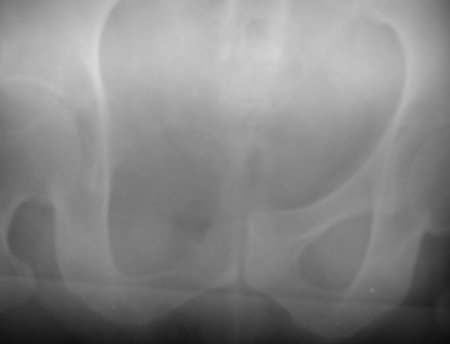

The right hip X-ray showed a lesion in the iliopubic branch (Figure 1) and the scintigraphy only captured this region (Figure 2).

Figura 1: Radiografia da pelve direita com lesão de rarefação óssea e focos de condensação.

Figure 1: Radiograph of the right pelvis with bone rarefaction lesion and condensation foci.